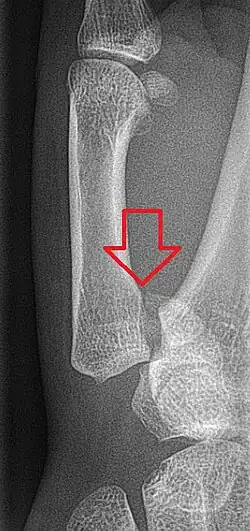

Bei der Bennett-Fraktur (auch Bennett-Luxationsfraktur) handelt es sich um eine Fraktur an der Basis des ersten Mittelhandknochens, die bis in das Daumensattelgelenk zieht. Der Mittelhandknochen wird durch den Zug der hier ansetzenden Sehne des M. abductor pollicis longus nach proximal verschoben. Meist bleibt ein kleineres dreieckiges Fragment ulnar am Gelenk stehen.

Von der Bennett-Fraktur abzugrenzen sind Frakturen der Basis des ersten Mittelhandknochens, die nicht in das Gelenk ziehen (Winterstein-Fraktur). Eine Bennett-Fraktur mit einem Trümmerbruch wird als Rolando-Fraktur bezeichnet.